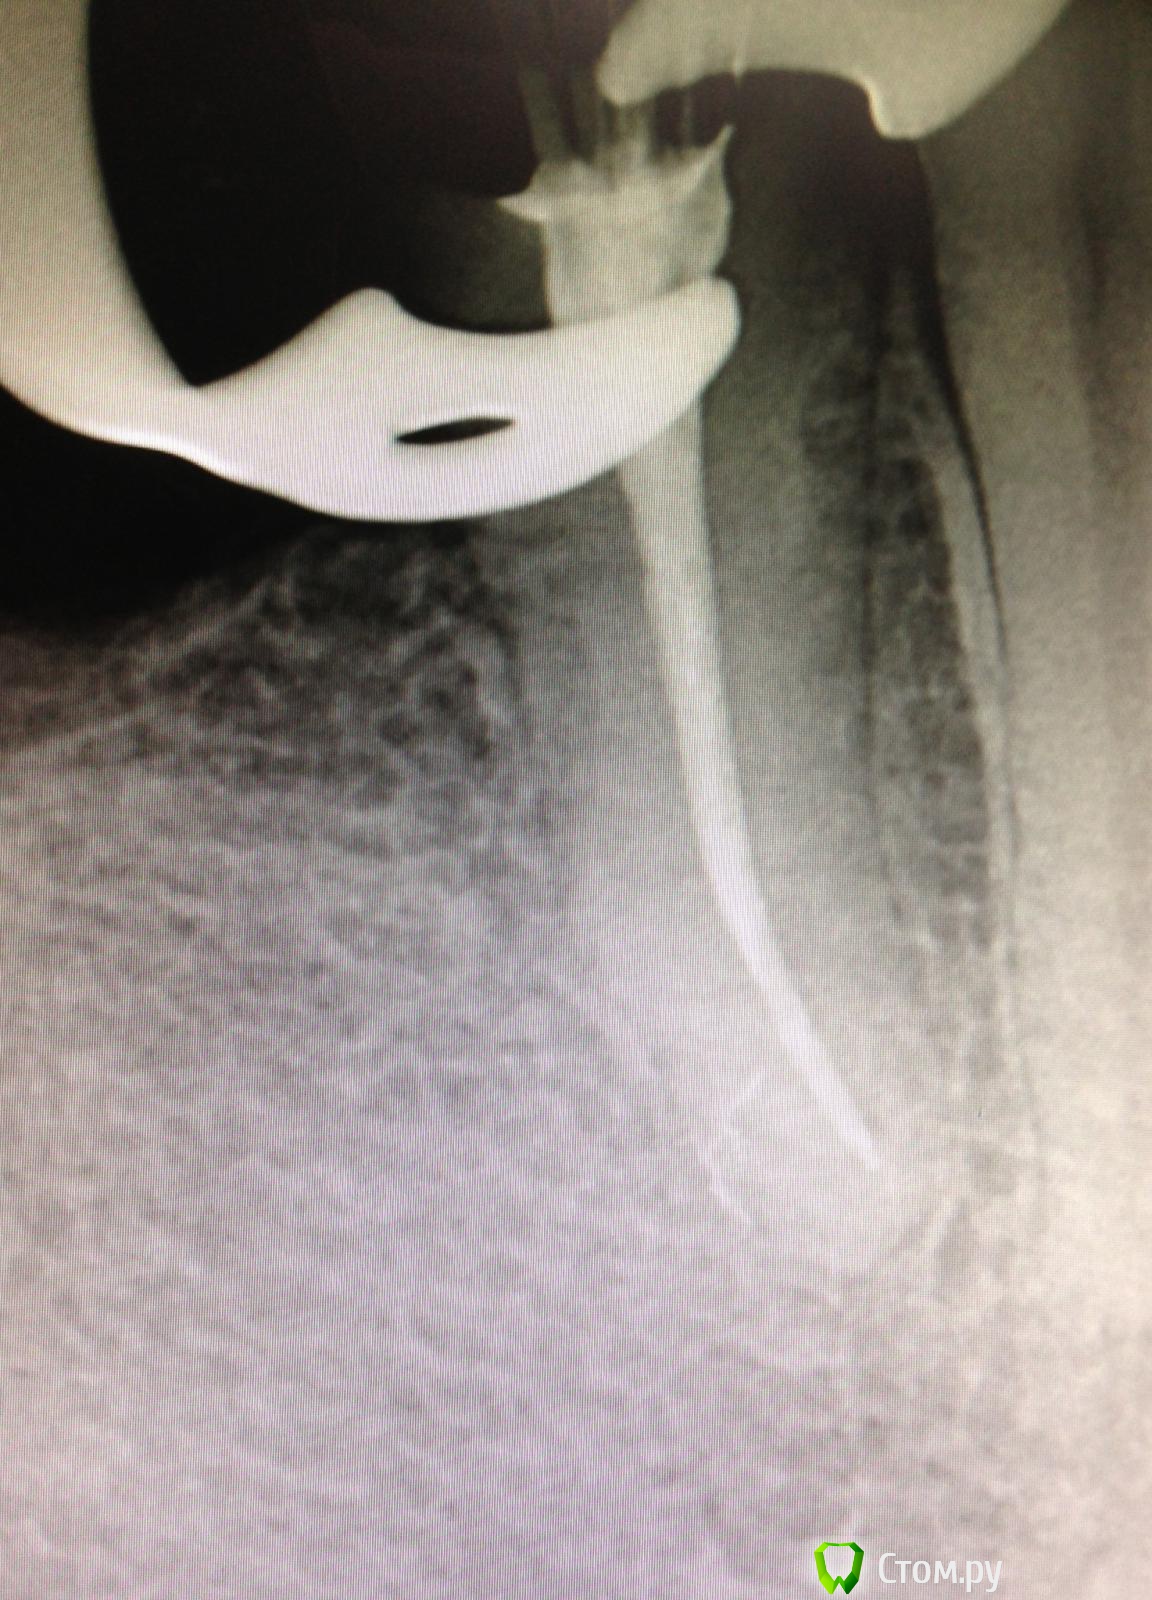

SSTi Опубликовано 22 ноября, 2014 Автор Поделиться Опубликовано 22 ноября, 2014 26. Хронический апикальный периодонтит. Пропущенный мб2. Зуб лечили год назад в гсп. Платно. И весь год он болел. Постоянные слабые боли. Переуссия +. 1 визит - коффердам, доступ, распломбировка мб, дб, небного. Поиск мб2. Обработка 4 каналов - протейпер д2,д3, профайлы - небный до 45.04. , мб и дб до 35.04, мб2 до 30.04. Гипохлорит, эдта, хлоргексидин, уз. Кальций. 2 часа. Второй визит - болей нет. Переуссия б/б. Вымыли кальций, еще моемся долго, латералка ( ан+ ). 2 часа. Ссылка на комментарий